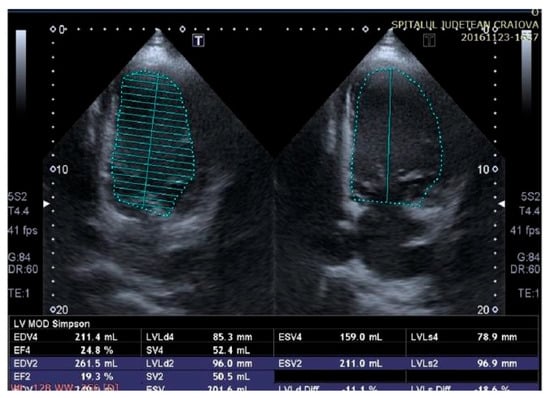

Figure 5.

Two-dimensional echocardiography revealed an improvement in left ventricular (LV) function with a low LV ejection fraction (LVEF) of 25% assessed according to the modified Simpson method, after therapy with a cardiac resynchronization device.